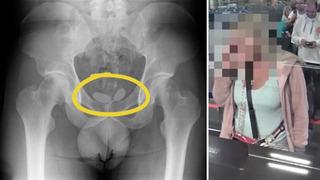

Röntgende ortaya çıktı! Uyuşturucuyu prezervatiflerin içine koyup cinsel organına gizlemiş

İzmir polisi, yurt dışından kente uyuşturucu getireceğinin istihbaratını alması üzerine tespit edilen 5 kişiyi İzmir Adnan Menderes Havalimanı’nda yakalarken, akıl almaz bir manzarayla karşılaşıldı. Yapılan muayenede, genç kadının uyuşturucuları prezervatifler içine koyup cinsel organına gizlediği, diğer erkek şahsın ise uyuşturucuları anüsüne yerleştirdiği tespit edildi.